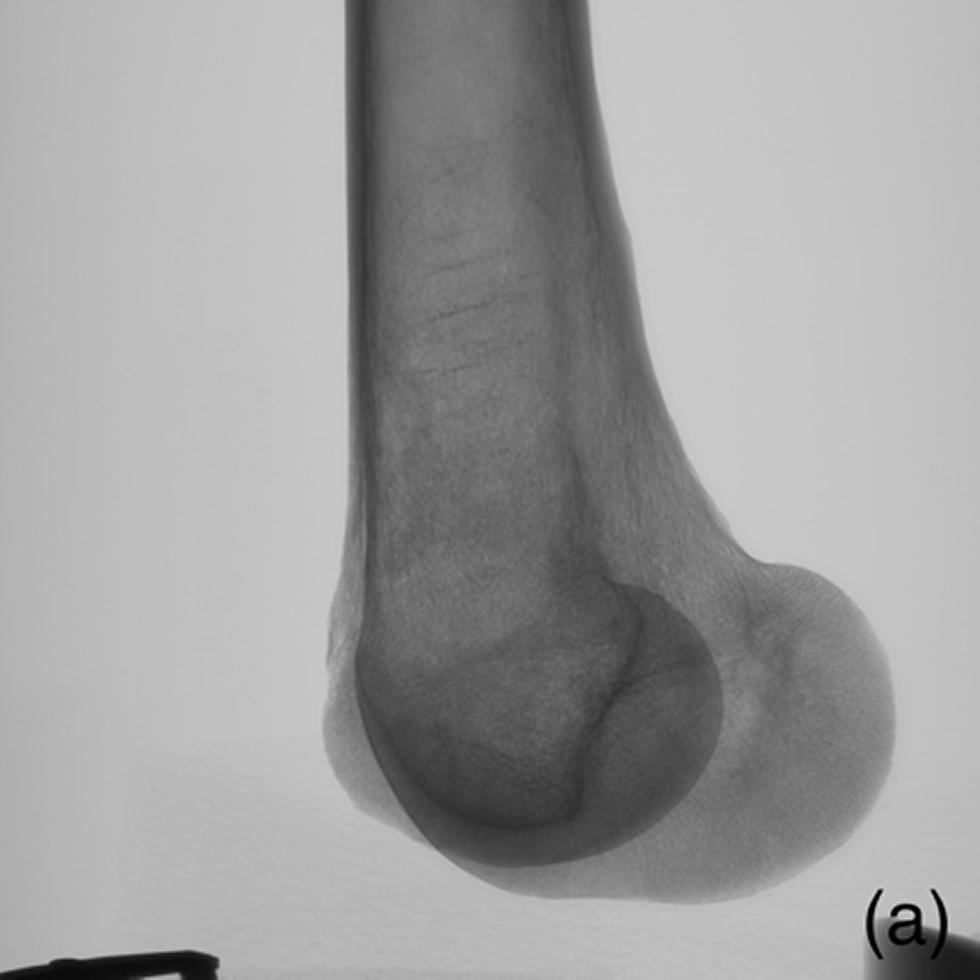

Figures - Example of radiographs acquired during CT scanning for lowest section.

Example of radiographs acquired during CT scanning for lowest section